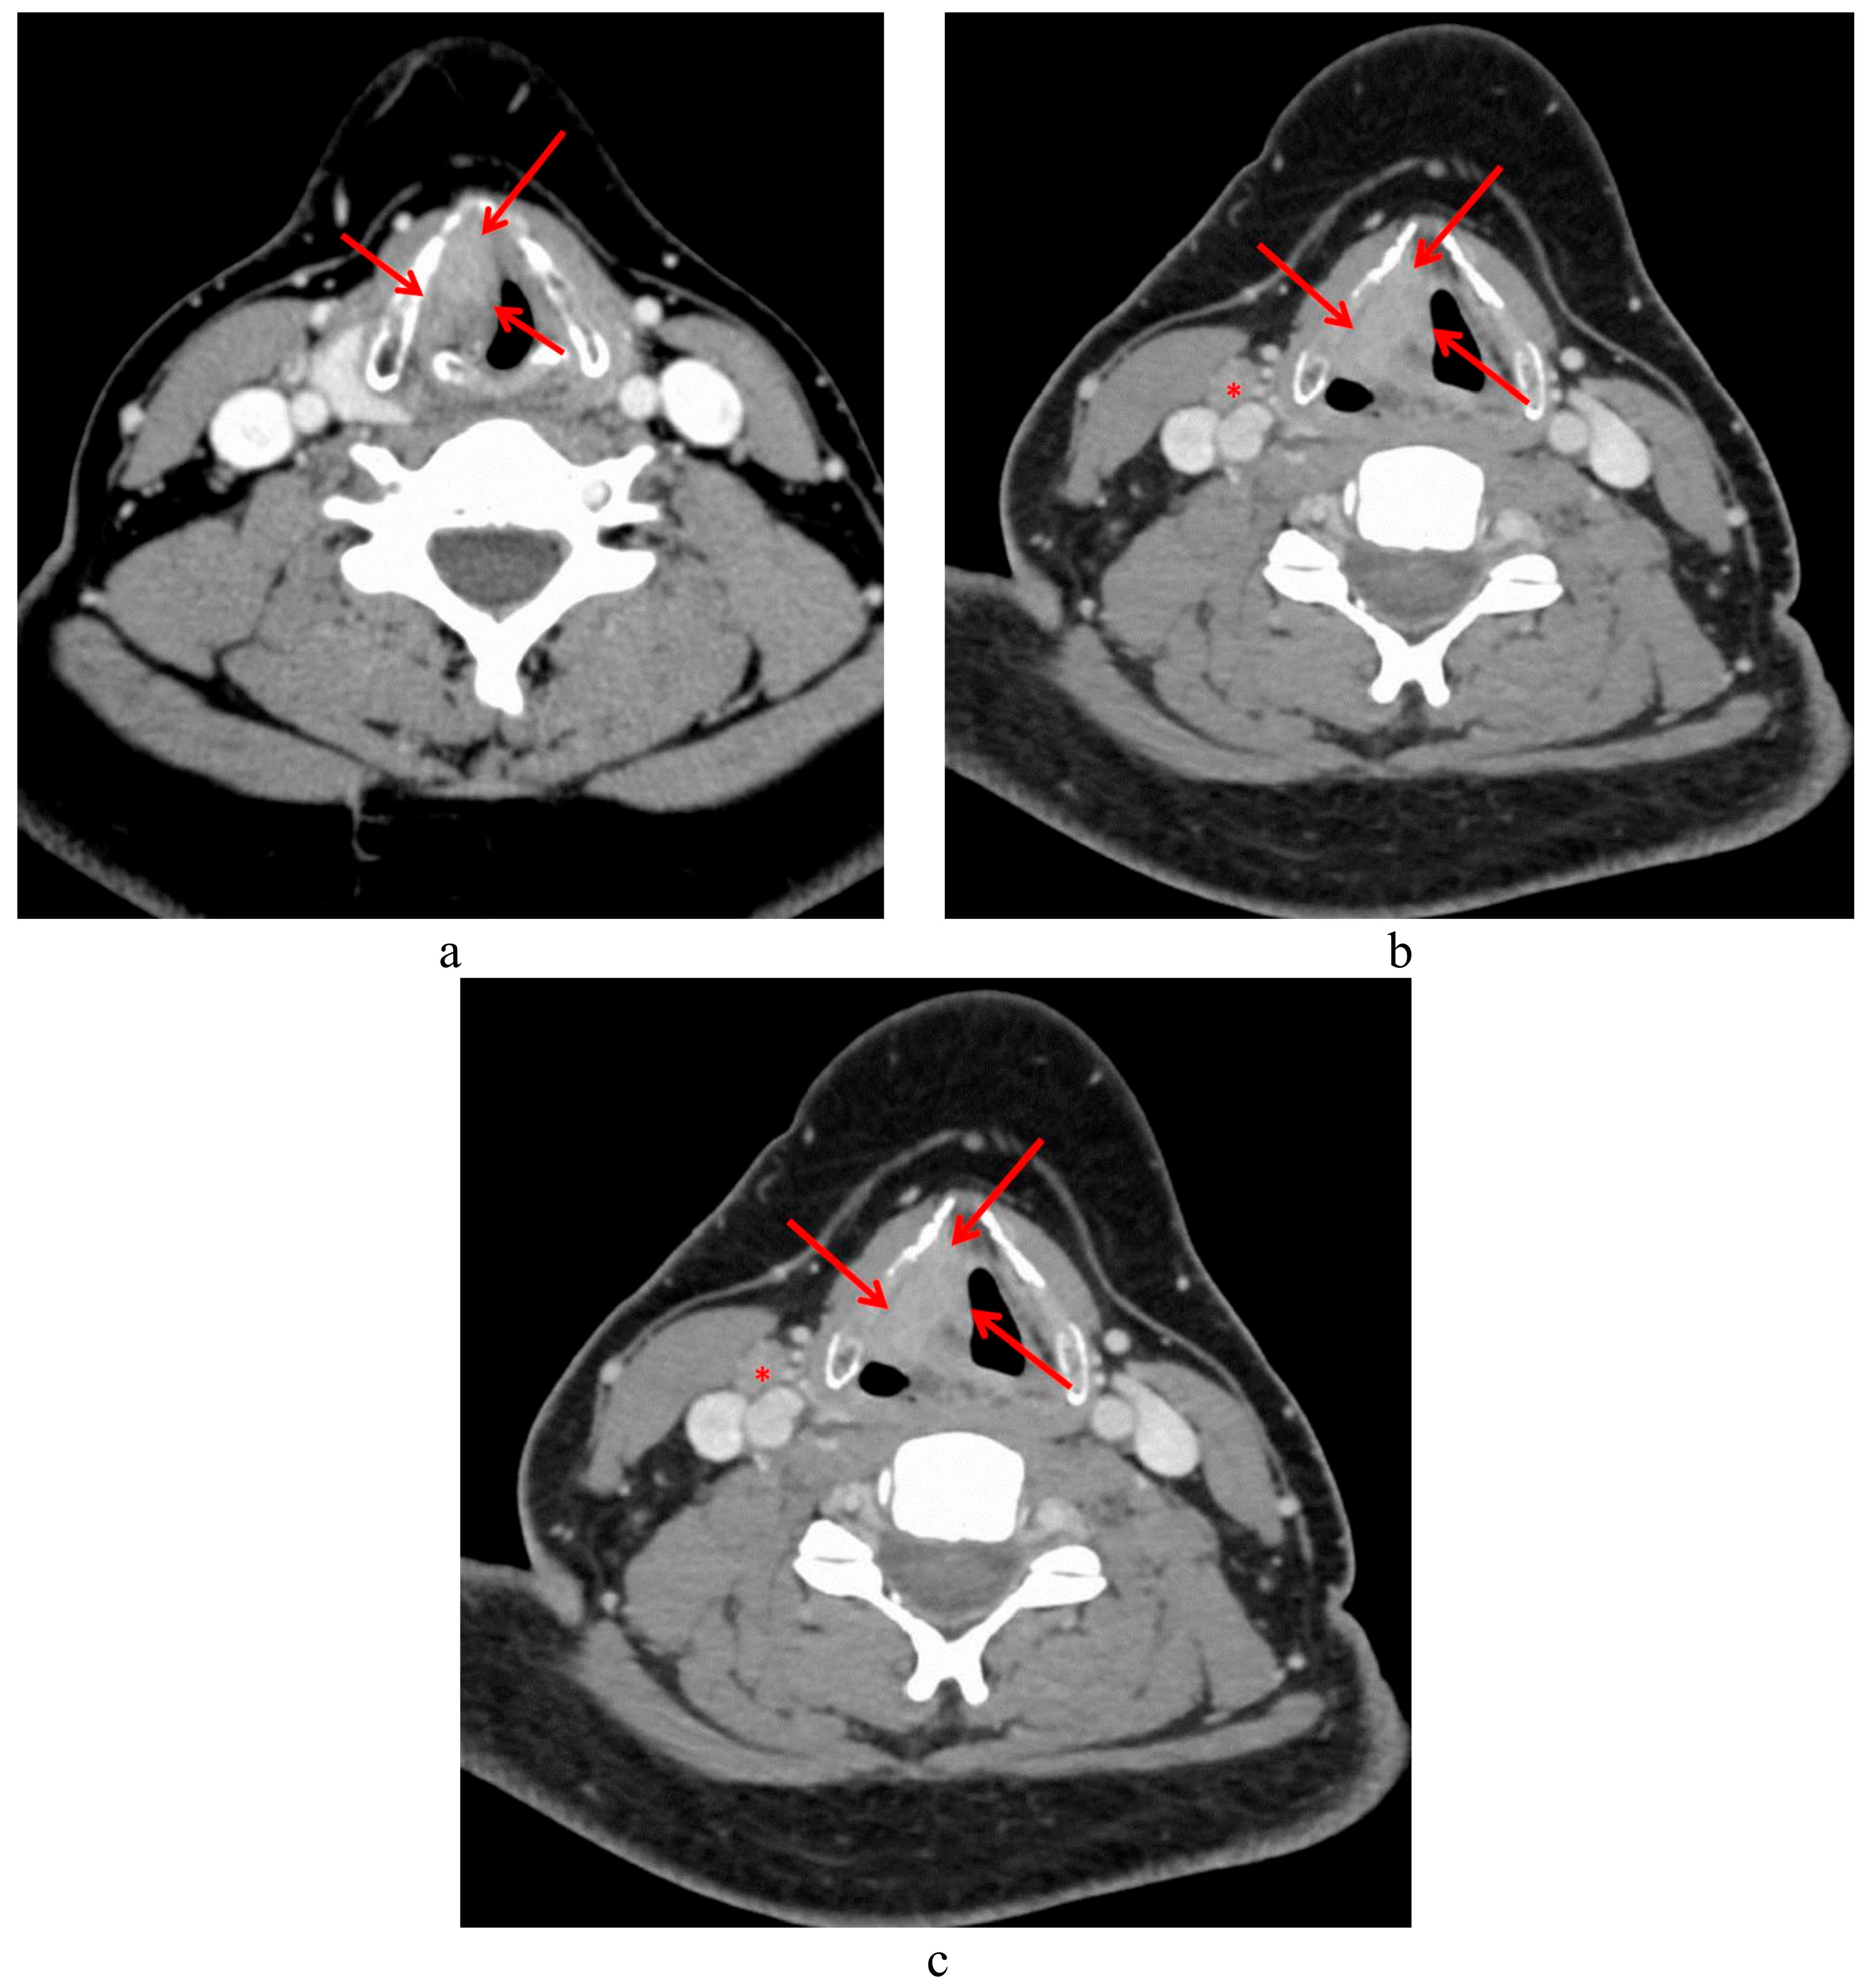

3.1. T4a Primary Tumors